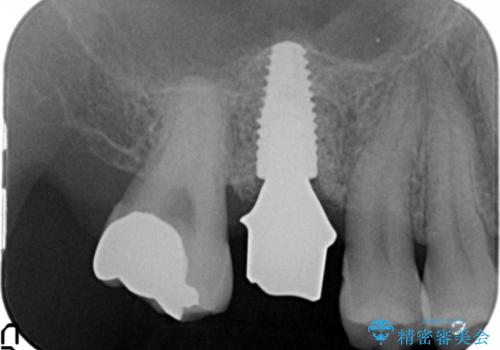

骨量が不十分であった為、ソケットリフトを併用しインプラントによる補綴計画を立てます。

ソケットリフトについて

上顎のインプラントは、上顎洞底までの距離が短い場合ソケットリフト法を行い骨量を増やしたのちにインプラント埋入を行うことでより長期的な予後を見込むことができます。

- 50万円(ストローマンインプラント・ソケットリフト・ジルコニアカスタムアバットメント・ジルコニアクラウン)費用は治療当時の料金となります